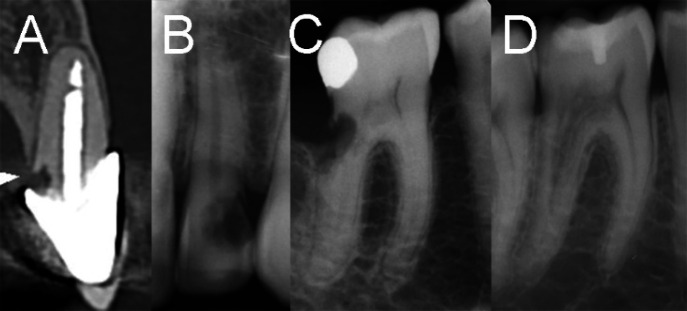

Invasive cervical root resorption (ICRR) is a dental pathology, marked by unexpected destruction originating in the cervical region of the tooth. This comprehensive literature review provides a holistic view into the pathogenesis, clinical manifestation, and precise management of ICRR, aiming to guide endodontists and enhance patient care and treatment outcomes. The review delves into the potential etiology of ICRR, covering contributing factors such as trauma, orthodontic treatment, and other pertinent conditions. It outlines the clinical and radiographic indicators, underscoring the crucial role of early detection and precise diagnosis in effectively managing and halting ICRR progression. The exploration of treatment approaches is thorough, ranging from non-surgical methods like vital pulp therapy or root canal treatment to surgical interventions. This review accentuates the essential role of interdisciplinary collaboration among diverse dental specialties in enhancing ICRR management. It highlights the importance of a consolidated strategy in enhancing treatment outcomes and preserving tooth structure and function. Moreover, it investigates prevention methods, risk evaluation, and identifies prospective research pathways to address the existing knowledge gaps.